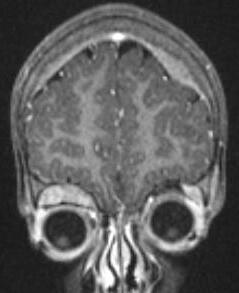

부신 종양 발생률 및 예후 | |

![]() | |